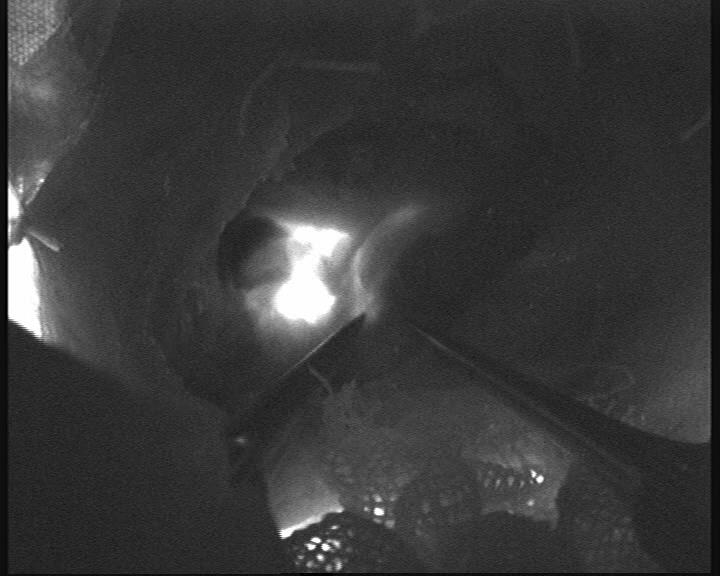

手术由神经外科缪星宇主任医师及马勃博士完成。团队在吲哚菁绿荧光显微镜引导下,通过颈部微小切口精准定位颈深淋巴结群与颈静脉,利用超显微外科技术,通过“八爪鱼”吻合方式吻合颈深淋巴-颈外静脉,建立两者间生理性引流通道,术中荧光造影引流通畅。双侧手术历时3小时余顺利完成,术中出血量不足10ml。术后患者生命体征平稳,术后2小时即恢复自主活动能力,焦虑情绪显著缓解。目前团队正密切监测其长期认知功能及影像学变化,进一步验证手术疗效。

图一 缪星宇主任医师显微镜下行颈深淋巴-颈外静脉吻合术